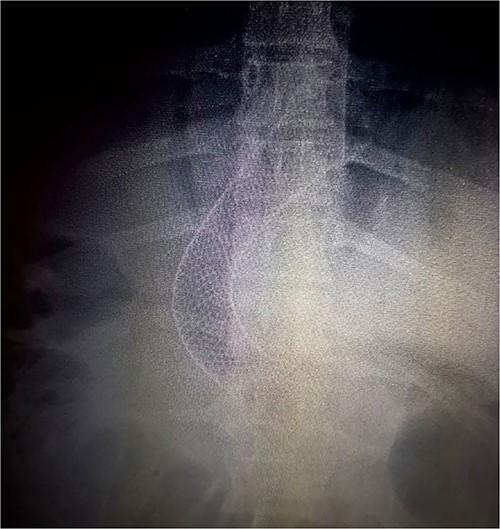

The following day (13 January 2021), an endoscopy was performed, revealing a leakage site at the mid-third of the gastric sleeve. A 12 cm esophagogastric stent was placed ~3–4 cm above the gastroesophageal junction (Fig. 3).

Thorax X-ray showing the placement of the gastroesophageal stent above the gastroesophageal junction.